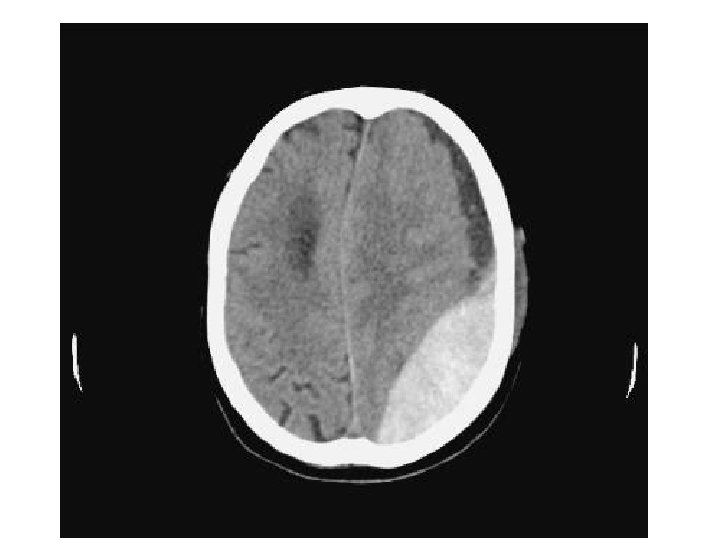

Les différentes lésions 2/2 • Hématome extra-dural – L'hématome extra-dural ou épidural est une accumulation de sang entre l'os du crâne et la dure-mère (enveloppe fibreuse du cerveau faisant partie des méninges). L'hématome extra-dural est une urgence chirurgicale absolue. Il se développe en quelques heures et peut entraîner la mort du patient par engagement cérébral si rien n'est fait. • Hématome sous-dural – Il s'agit d'un épanchement sanguin situé entre, en dehors la dure-mère, et en dedans l’arachnoïde. Il peut survenir de façon aiguë, au cours des heures suivant le traumatisme (hématome sous-dural aigu). Il est alors fréquemment associé à une contusion cérébrale dont peut dépendre le pronostic. Il peut aussi se constituer à bas bruit, et se démasquer quinze jours, voire des semaines après un traumatisme relativement peu important (hématome sous-dural chronique). • Hémorragie intracérébrale – Il s'agit d'un saignement à l'intérieur du parenchyme cérébral. • Hémorragie méningée – Une hémorragie méningée est observée dans 1/3 des traumatismes crâniens sévères. Elle peut être secondaire à la lésion d'un vaisseau méningé, ou bien à une suffusion hémorragique à partir d’un foyer de contusion du cortex cérébral.